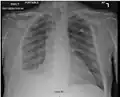

For uncomplicated silicosis, chest x-ray will confirm the presence of small (< 10 mm) nodules in the lungs, especially in the upper lung zones. Using the ILO classification system, these are of profusion 1/0 or greater and shape/size "p", "q", or "r". Lung zone involvement and profusion increases with disease progression. In advanced cases of silicosis, large opacity (> 1 cm) occurs from coalescence of small opacities, particularly in the upper lung zones.

With retraction of the lung tissue, there is compensatory emphysema. Enlargement of the hilum is common with chronic and accelerated silicosis. In about 5–10% of cases, the nodes will calcify circumferentially, producing so-called "eggshell" calcification. This finding is not pathognomonic (diagnostic) of silicosis. In some cases, the pulmonary nodules may also become calcified.

Chest X-ray showing uncomplicated silicosis